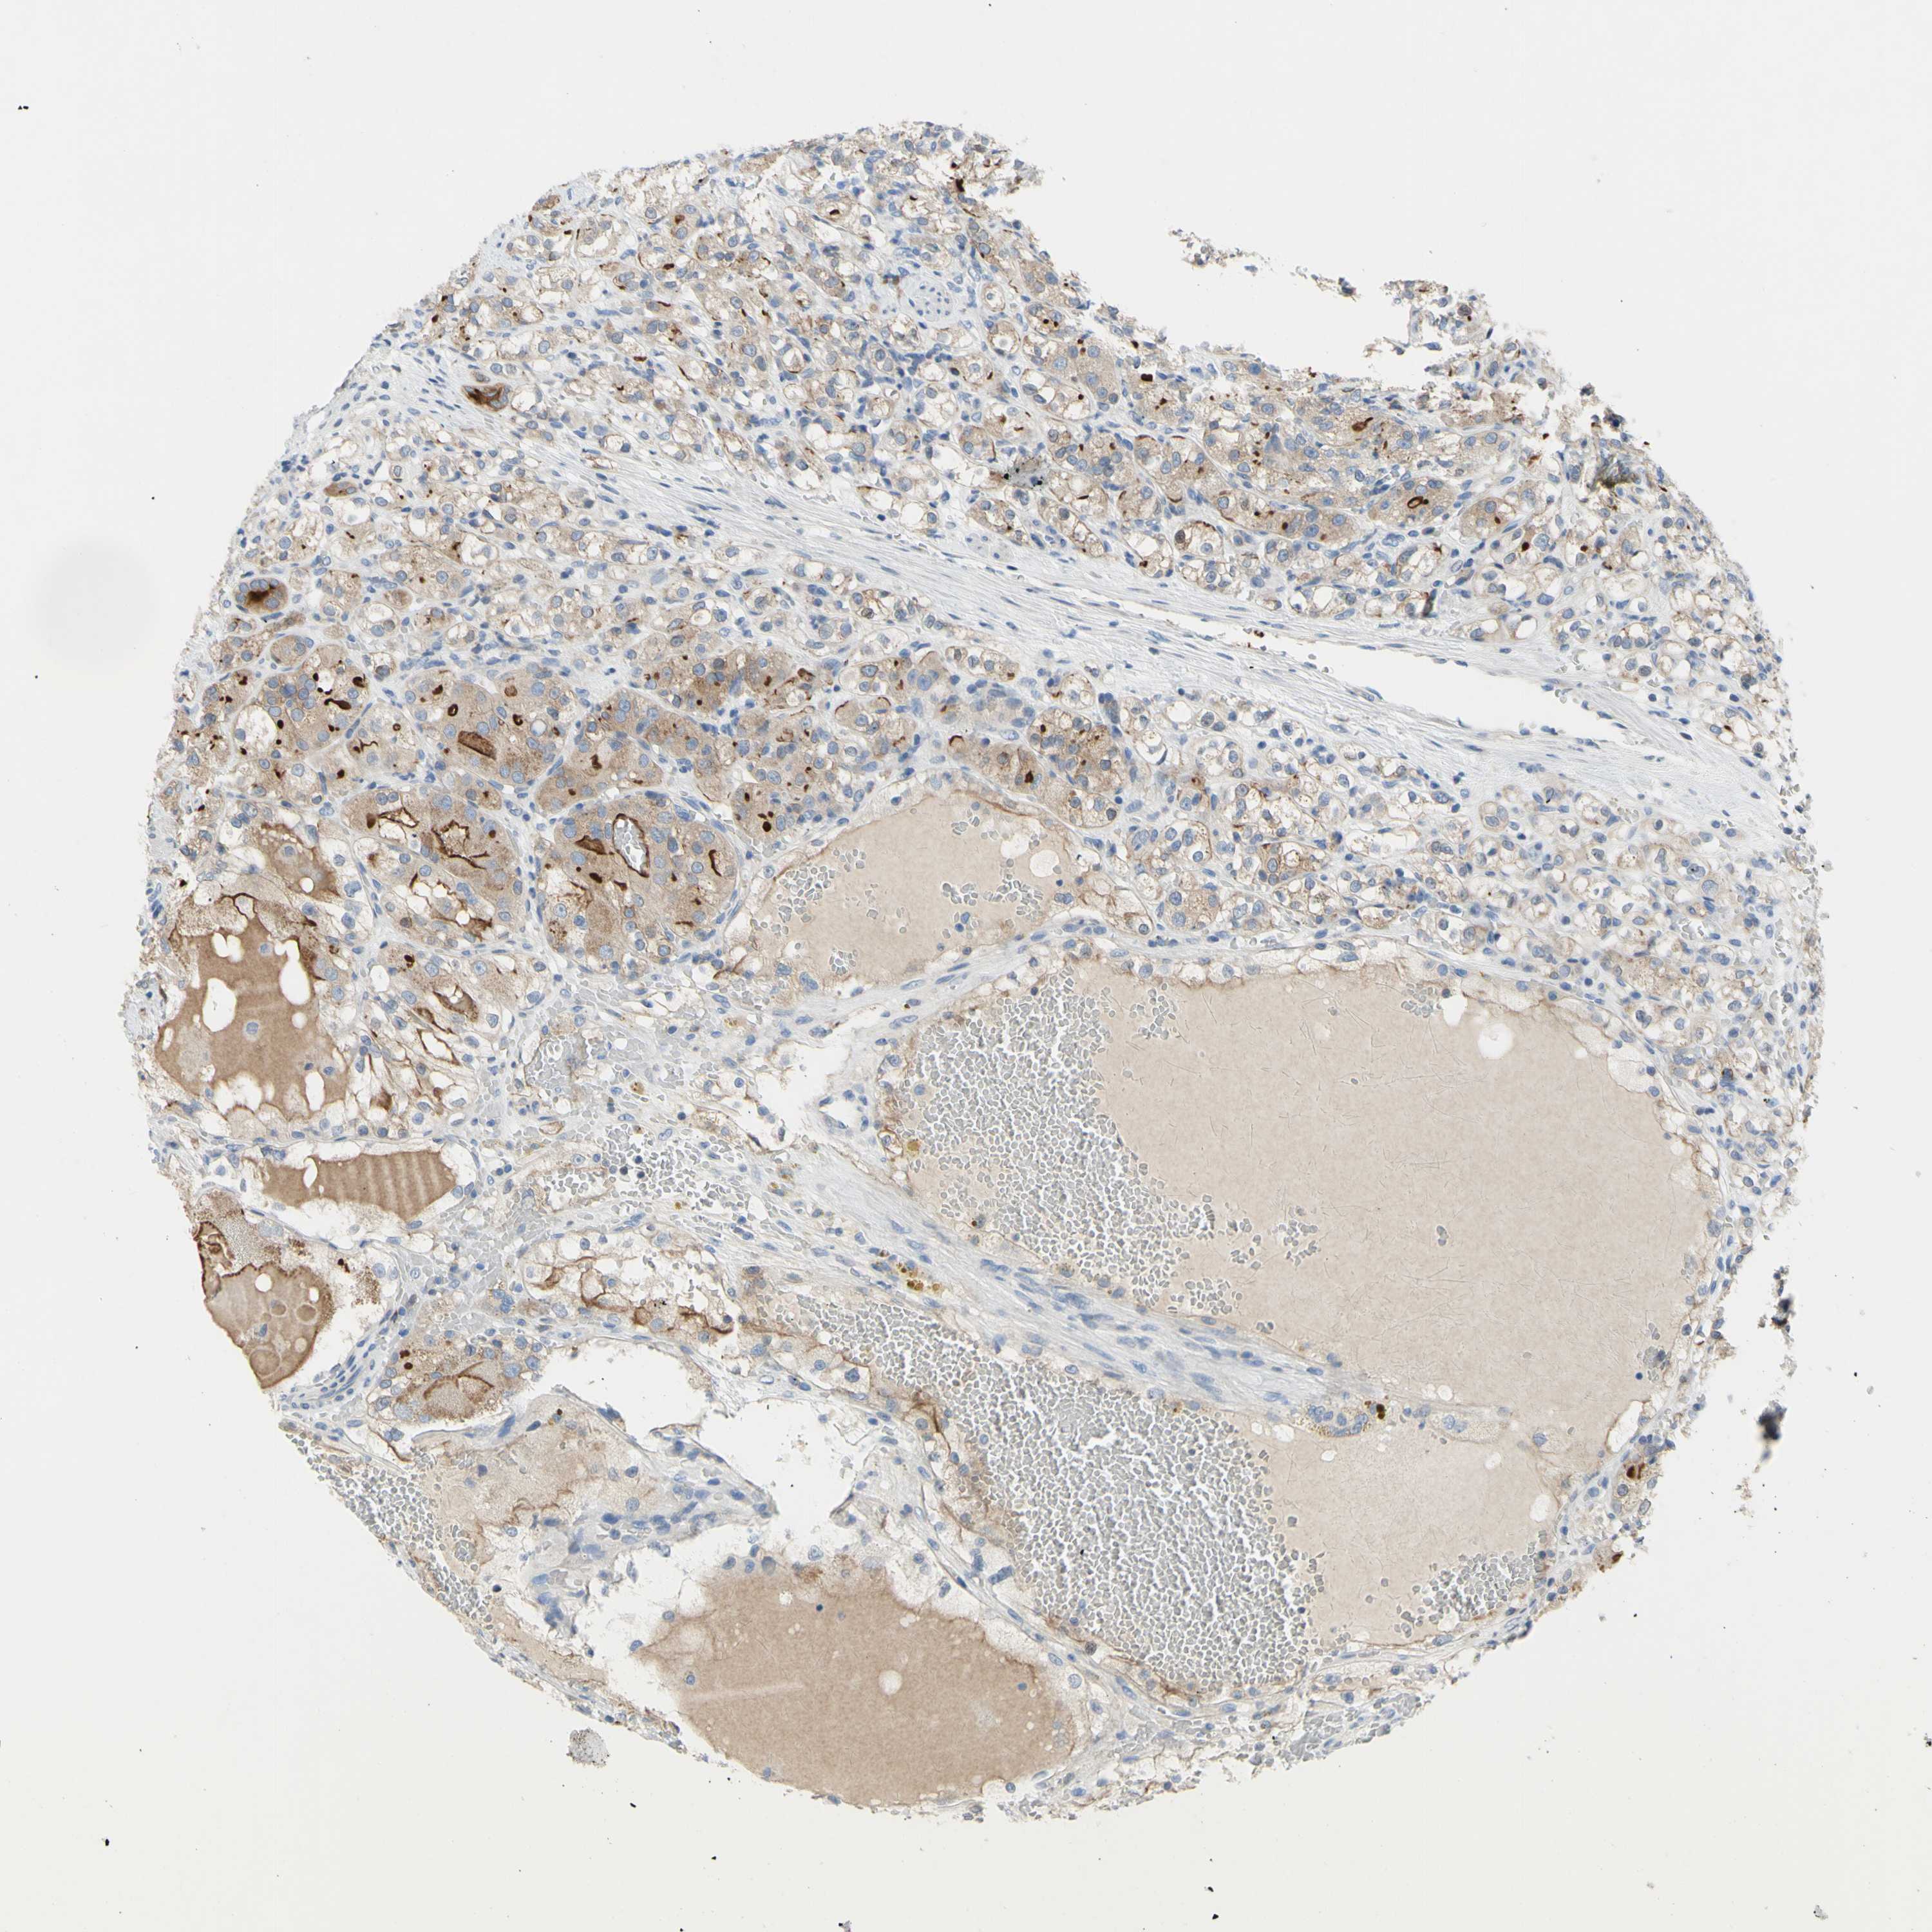

KIDNEY RENAL CLEAR CELL CARCINOMA (VALIDATION) - Interactive survival scatter ploti

The Survival Scatter plot shows the clinical status (i.e. dead or alive) for all individuals in the patient cohort, based on the same data that underlies the corresponding Kaplan-Meier plots. Patients that are alive at last time for follow-up are shown in blue and patients who have died during the study are shown in red.

The x-axis shows the expression levels (FPKM) of the investigated gene in the tumor tissue at the time of diagnosis. The y-axis shows the follow-up time after diagnosis (years). Both axes are complimented with kernel density curves demonstrating the data density over the axes. The top density plot shows the expression levels (FPKM) distribution among dead (red) and alive patients (blue). The right density plot shows the data density of the survived years of dead patients with high and low expression levels respectively, stratified using the cutoff indicated by the vertical dashed line through the Survival Scatter plot. This cutoff is automatically defined based on the FPKM cutoff that minimizes the p-score. The cutoff can be changed by dragging the vertical line or by entering a cutoff value in the square labeled "Current cut-off".

Under the Survival Scatter plot the p-score landscape (black curve; left axis) is shown together with dead median separation (red curve; right axis). Dead median separation is the difference in median mRNA expression between patients who have died with high and low expression, respectively. It is calculated as follows: median FPKM expression of dead patients with high expression - median FPKM expression of dead patients with low expression. This is intended to aid the user in visually exploring custom cutoffs and the associated p-scores and dead median separation.

Individual patient data is displayed and can be filtered by clicking on one or more of the category buttons on the top of the page. Categories describing expression level and patient information include: high, low, alive, dead, female, male and tumor stages. The scale of the x-axis can be toggled between linear and log-scale by clicking on the "x log" button. Mouse-over function shows TCGA ID, patient information and mRNA expression (FPKM) for each patient.

& Survival analysisi

Kaplan-Meier plots summarize results from analysis of correlation between mRNA expression level and patient survival. Patients were divided based on level of expression into one of the two groups "low" (under cut off) or "high" (over cut off). X-axis shows time for survival (years) and y-axis shows the probability of survival, where 1.0 corresponds to 100 percent.

MUC1 is not prognostic in Kidney Renal Clear Cell Carcinoma (validation)

Best expression cut offi

Based on the FPKM value of each gene, patients were classified into two groups and association between prognosis (survival) and gene expression (FPKM) was examined. The best expression cut-off refers the FPKM value that yields maximal difference with regard to survival between the two groups at the lowest log-rank P-value. Best expression cut-off was selected based on survival analysis .

When clicking on this number, the vertical dashed line indicating cut-off, the interactive survival plot, and the Kaplan-Meier curve will be adjusted to show results based on the best expression cut-off.

: 24.39

TCGA RNA samplesi

RNA-seq data is reported as average FPKM (number Fragments Per Kilobase of exon per Million reads), generated by the The Cancer Genome Atlas (TCGA) .

Normal distribution across the dataset is visualized with box plots, shown as median and 25th and 75th percentiles. Points are displayed as outliers if they are above or below 1.5 times the interquartile range. FPKM values of the individual samples are presented next to the box plot.

Average pTPM 95.3

Number of samples 100